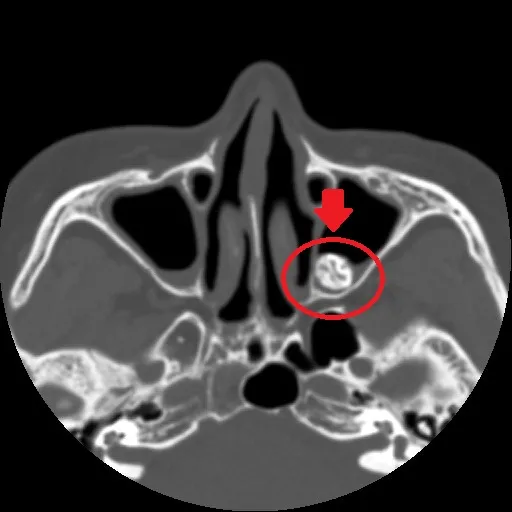

經安排核磁共振(MRI)檢查,赫然在患者的左上顎竇位置處發現一顆外型及密度都疑似「牙齒」的不明物體,研判是「異生齒」,且位置十分特別,若採取傳統手術,需先翻開上嘴唇內側牙齦部位,之後打洞鑽入鼻腔前壁取出,不僅傷口大,且術後癒合時間長,經溝通後,患者同意採用「自然孔」(鼻腔)執行手術,過程中透過磁導航3D立體定位系統,約30分鐘即取出約2公分大的異生齒。

田輝勣指出,「異生齒」是指牙齒生長在口腔齒槽以外的地方,常見多出現在上顎骨部位,而該婦人發生位置卻在鼻腔內,臨床出現機率極低,這類患者往往會引發感染及發炎,進而出現鼻涕倒流、流鼻血、鼻塞等疑似鼻竇炎症狀。

醫師建議民眾若有長期鼻竇炎症狀,務必就醫檢查,避免病情惡化。(圖為情境照,非當事人,亞大醫院提供)